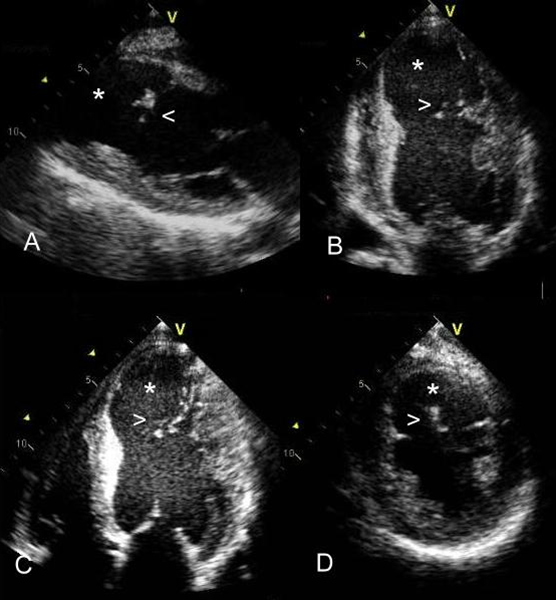

Figure 3. Echocardiographic views (A. Parasternal long axis view; B. Apical 2-chamber view; C. Apical 4-chamber view; D. Parasternal short axis view of the left ventricle) revealing an apical dilatation of the left ventricle (see*), with small mobile intraventricular densities (arrow head) suggestive of a left ventricular aneurysm or a pseudoaneurysm.

Transthoracic echocardiogram (TEE) confirmed the severely depressed left ventricular ejection fraction and showed an apical dilatation of the left ventricle, with small, mobile, intraventricular densities that suggested loose myocardial tissue at the margins of the anterior and septal walls. This suggested a left ventricular aneurysm (LVA) or a pseudoaneurysm (PA) (Figure 3). Contrast echocardiography and cardiac CT angiography failed to distinguish between an LVA and a PA. Cardiac magnetic resonance (CMR) was therefore requested: this confirmed an LVA (Figure 4) with myocardial tissue hanging in the LV cavity, consistent with intramyocardial dissection of the LV anterior, septal, and apical myocardial walls (Figure 5).